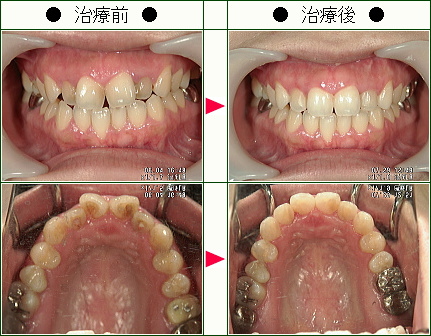

☆歯のデコボコ矯正症例(M.K.様 35歳 女性)